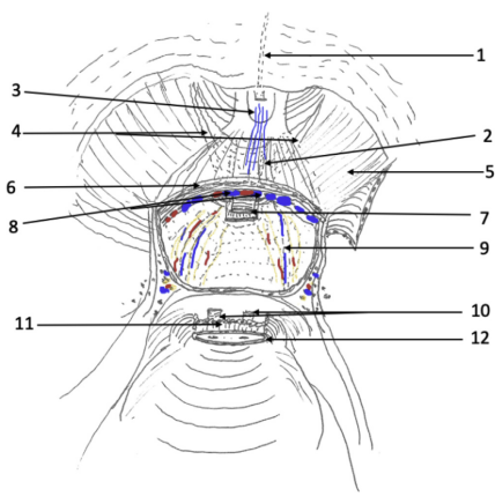

Los tumores testiculares no seminomatosos en etapa I tienen un riesgo de presentar micro metástasis en el retroperitoneo cercano al 30% de los casos, especialmente, si hay factores de riesgo en la biopsia del tumor testicular. Es hasta ahora controvertida la opción terapéutica a ejecutar y la linfadenectomía lumboaórtica (LALA) es una de ellas. También tema actual de controversia es la conveniencia de realizar la uni o bilateralidad de la linfadenectomía. La gran ventaja de la LALA es que tiene cerca de un 100% de sensibilidad y especificidad, aún en la era de la tomografía por emisión de positrones (PET) y representa una alternativa a los protocolos de observación (40-42). Sin ahondar en la controversia, explicaremos en forma sencilla esta técnica cuya mayor complejidad reside en el posible daño a un vaso mayor pudiendo transformar un procedimiento reglado en una emergencia. Otro aspecto a considerar es la edad del paciente en que la preservación de la función eyaculatoria es fundamental. En estos casos la ubicación del paciente es igual que la anteriormente descrita para la cirugía renal. Utilizamos el trócar de la cámara en la cicatriz umbilical y el trócar más caudal desplazado hacia la fosa ilíaca correspondiente. Una vez logrado el pneumoperitoneo, tan importante como la minuciosa extirpación del espécimen linfático, es lograr previamente una amplia exposición de los límites a disecar: si el límite superior es la vena renal, la disección debe abarcar al menos unos centímetros sobre el hilo renal y lo mismo para los demás límites. De esta manera se podrá efectuar un procedimiento cómodo, completo y seguro. Muchas veces se falla en estos detalles básicos que pueden frustrar el éxito de la cirugía y poner en riesgo al paciente. Indistintamente del lado, el abordaje que realizamos es transperitoneal. Hay limitadas experiencias de abordaje retroperitoneal que no han sido suficientemente reproducidas y podrían tener su espacio solo en excepcionales circunstancias(43). En ambos casos es necesario movilizar ampliamente el colon respectivo para exponer los grandes vasos y los límites de disección propuestos por Weissbach (Figura 31). Los límites superiores están determinados por el borde inferior de las venas renales y el límite inferior por el cruce del uréter sobre los vasos ilíacos. Los límites laterales están demarcados por los uréteres. En el lado derecho es necesario levantar el hígado y para esto utilizamos el Endo Retract™ II o también se puede utilizar una pinza de 5 mm desde el apéndice xifoides fijado en la pared costal. Es necesario realizar una maniobra de Kocher para movilizar el duodeno y exponer los grandes vasos al lado derecho. Logrado este tiempo, se extirpa todo el material linfático de las regiones para cava, supra cava e interaorto cava. Rutinariamente extirpamos los ganglios supra aórticos por sobre la arteria mesentérica inferior. Utilizamos una pinza y disector común para separar el espécimen linfático de las estructuras vasculares. Cuando tenemos una perfecta identificación de éstos, usamos un LigasureTM Maryland de 5 mm para sellar y seccionar los linfáticos. Evitamos seccionar los vasos lumbares ya que, dado que, de existir metástasis ganglionares, éstas se desarrollarían ventrales a los vasos(44). Una vez liberado el espécimen linfático, este se extrae en una bolsa de PVC por uno de los sitios de punción. Ocasionalmente después de establecida una rigurosa hemostasia, instalamos en el lecho quirúrgico una matriz hemostática con trombina sintética para disminuir el riesgo de un linfocele. Para el lado izquierdo realizamos el mismo procedimiento descrito anteriormente, evitando disecar y lesionar los nervios simpáticos responsables de la eyaculación anterógrada, ubicados por sobre la aorta debajo del nacimiento de la arteria mesentérica inferior (45) (Figura 32).